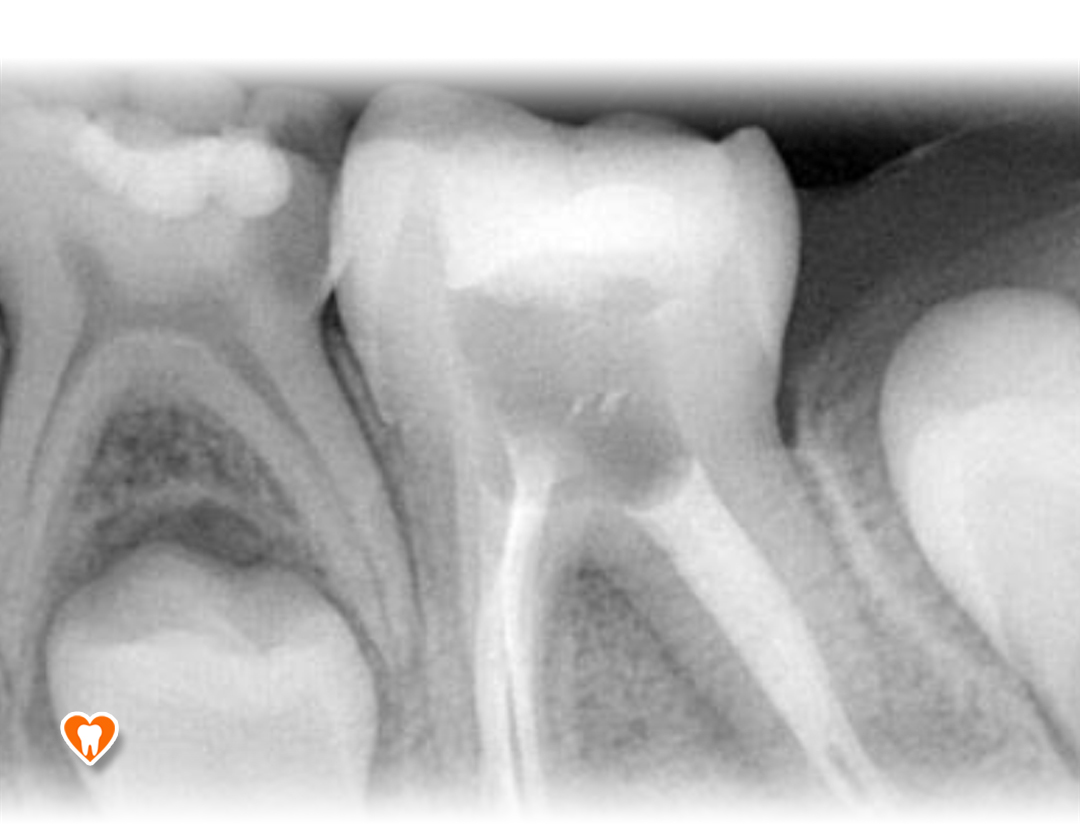

Zdjęcia radiologiczne:

• Punktowe

wykorzystywana jest w leczeniu próchnicy zębów oraz stanów zapalnych miazgi zęba i tkanek okołowierzchołkowych korzeni zębów. Charakteryzują się najwyższą rozdzielczością ze wszystkich badań radiologicznych.Prześwietlenie zęba daje dokładny obraz przebiegu korzeni zęba, ilości i stopnia zakrzywienia kanałów oraz wykrycia próchnicy na powierzchniach stycznych - niewidocznych podczas rutynowego badania stomatologicznego.

W naszym gabinecie, dzięki zastosowaniu najnowszych urządzeń do radiowizjografii firmy Carestream, dostosowujemy indywidualnie do każdego pacjenta dawkę promieniowania, niezbędną do wykonania zdjęcia, jednocześnie minimalizując ją, aby każdy pacjent był bezpieczny.